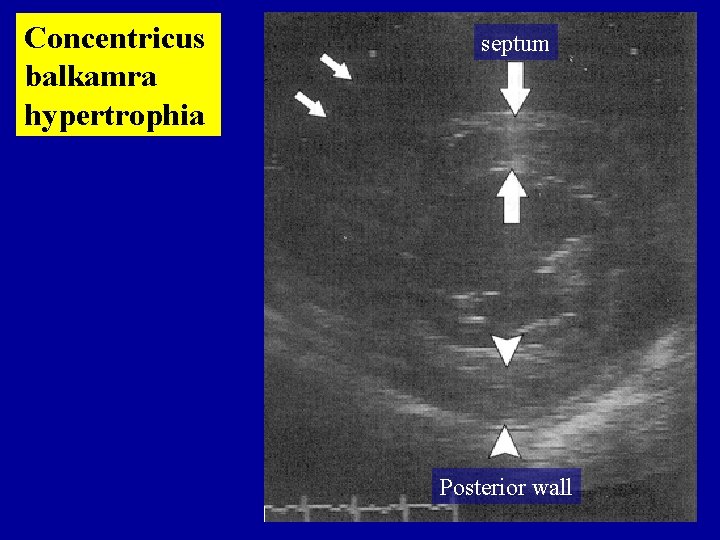

Concentricus balkamra hypertrophia septum Posterior wall